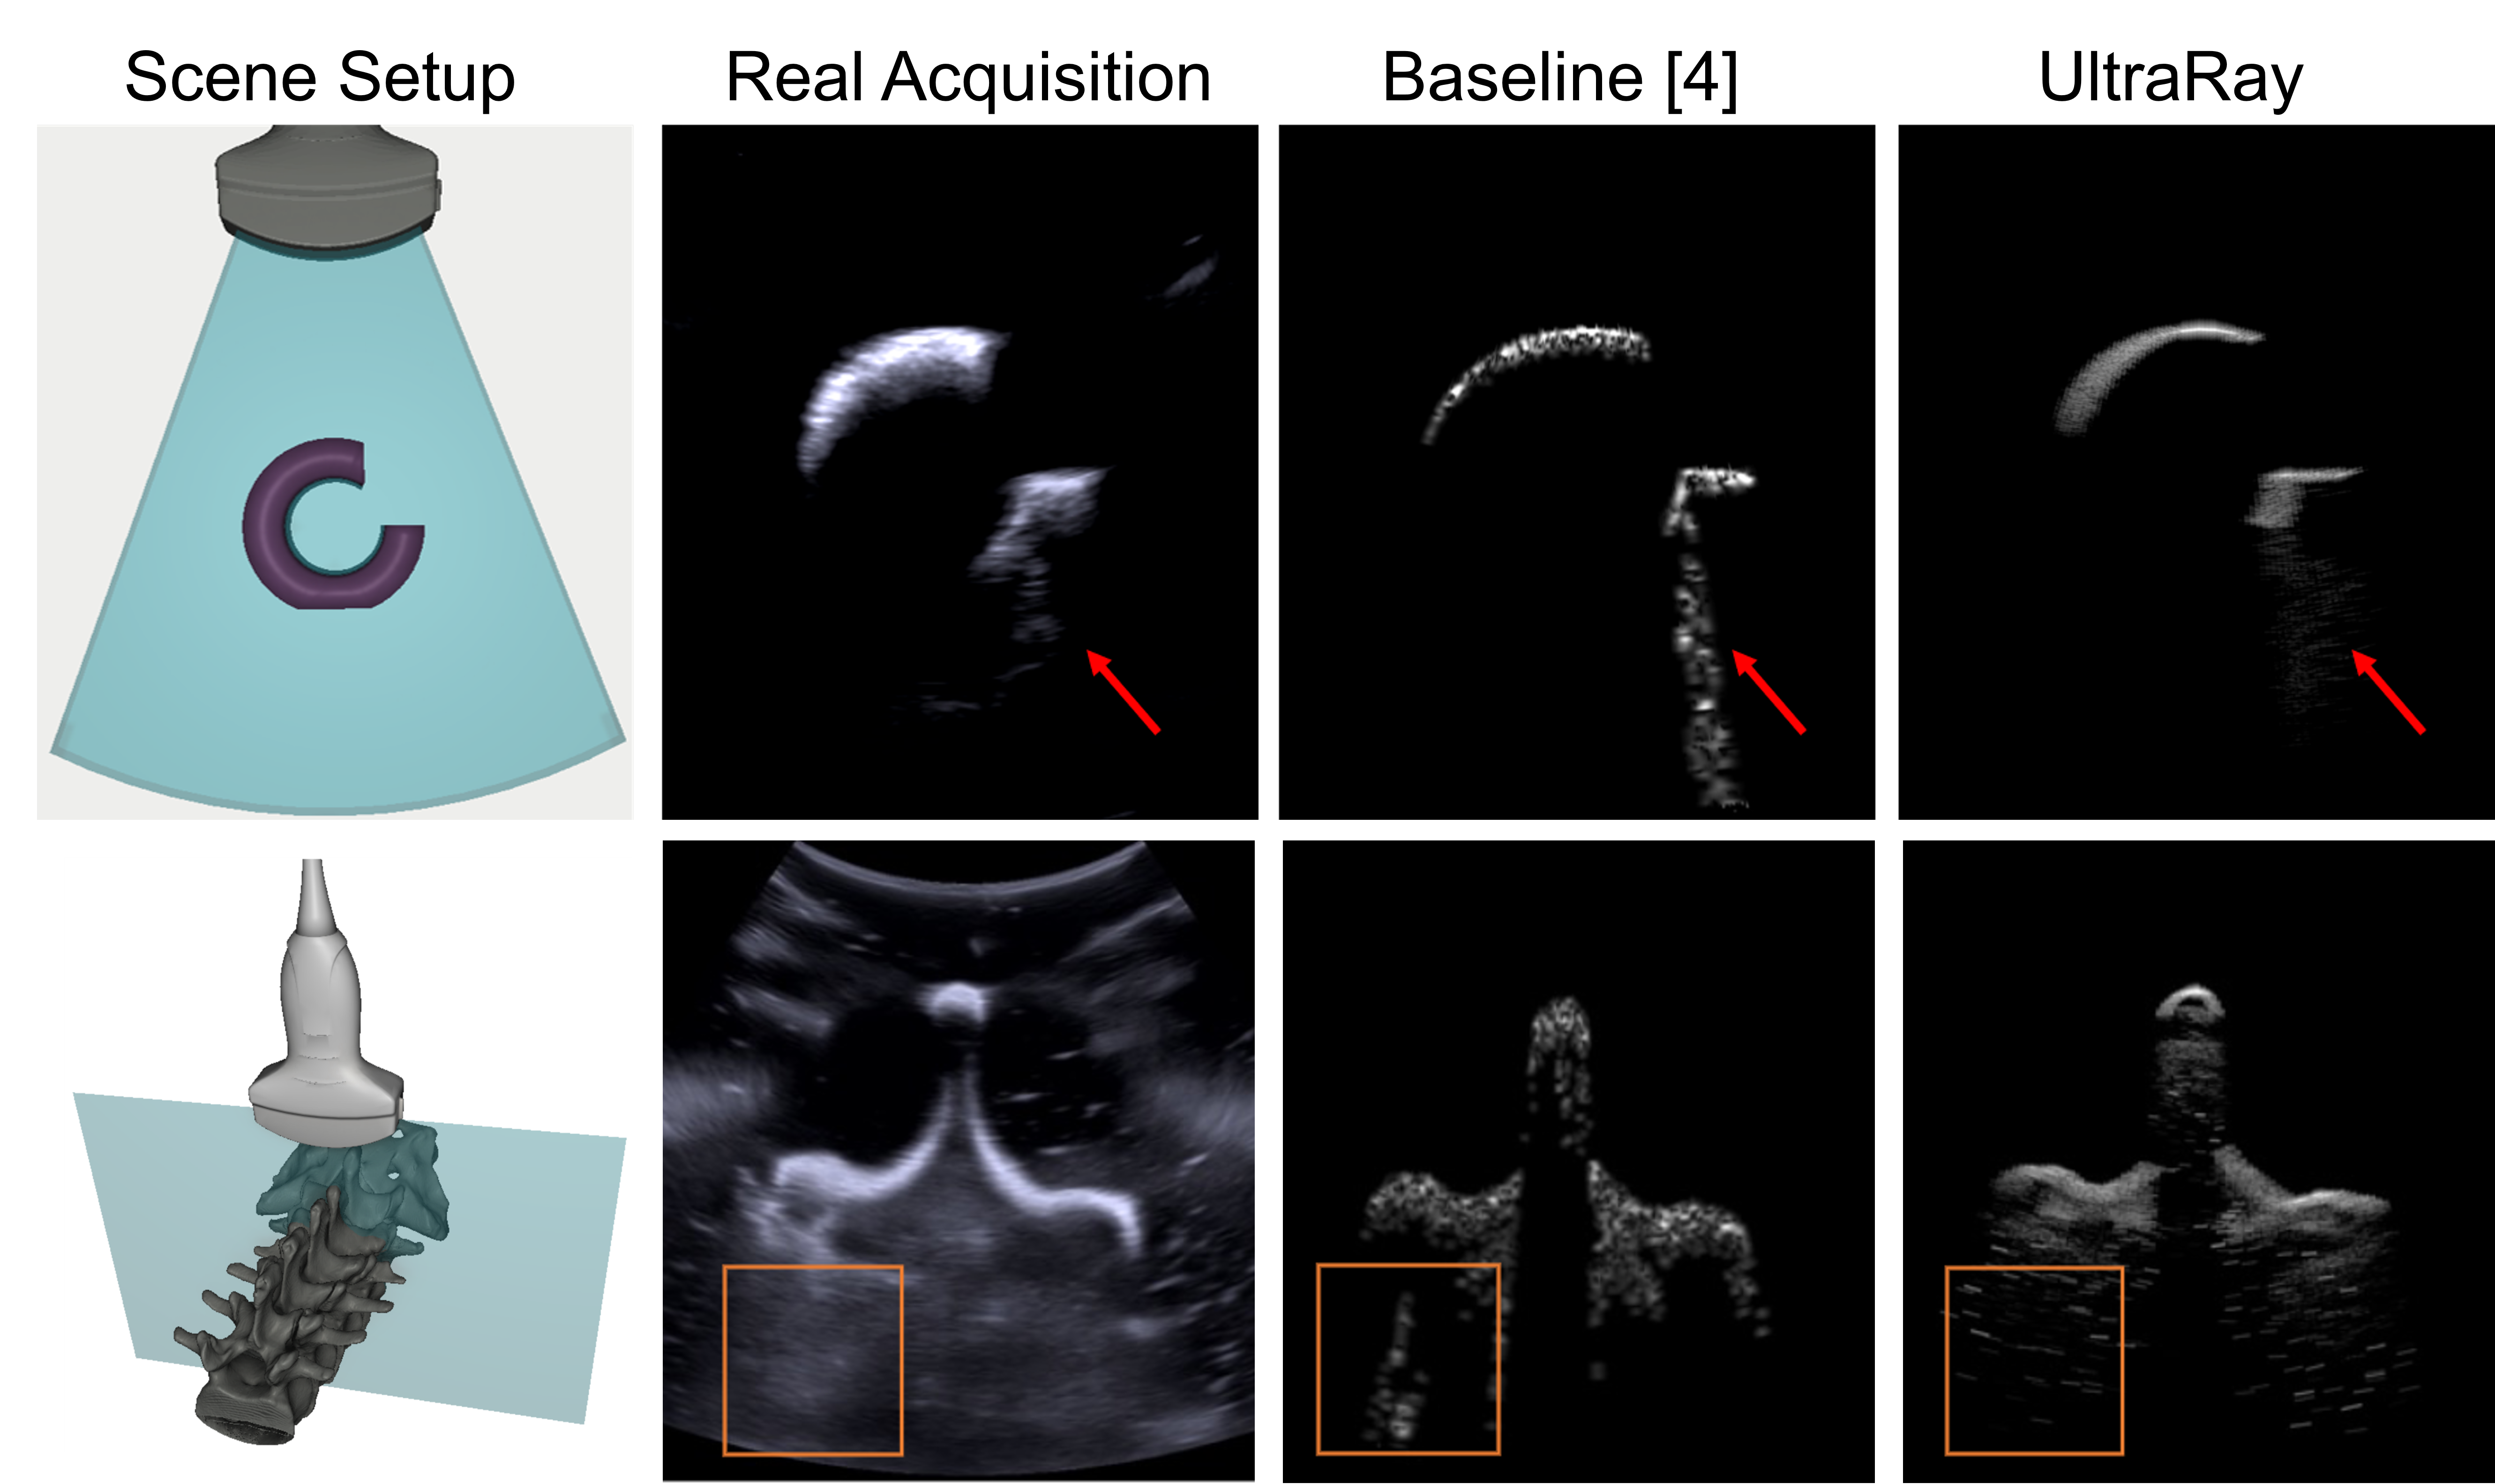

Results

UltraRay results figure